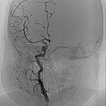

In der digitalen Subtraktionsangiographie (DSA) nach Injektion in die rechte Arteria carotis communis zeigt sich das Hämangiom wie erwartet vor allem aus der Arteria carotis externa versorgt.

Die Übersichtsangiographie über die Arteria carotis communis nach Entfernung des venösen Blockballons zeigt ein praktisch komplett devaskularisiertes Hämangiom. Die intracerebrale Zirkulation ist unauffällig.